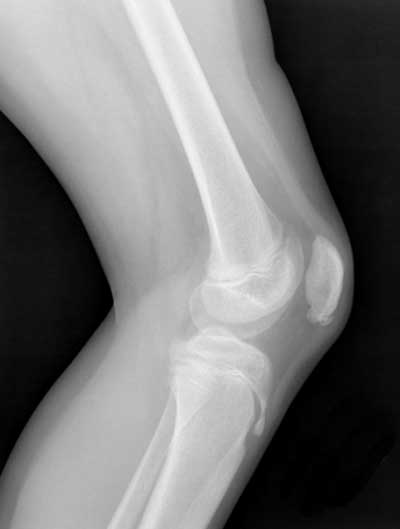

- Osgood-Schlatter Disease